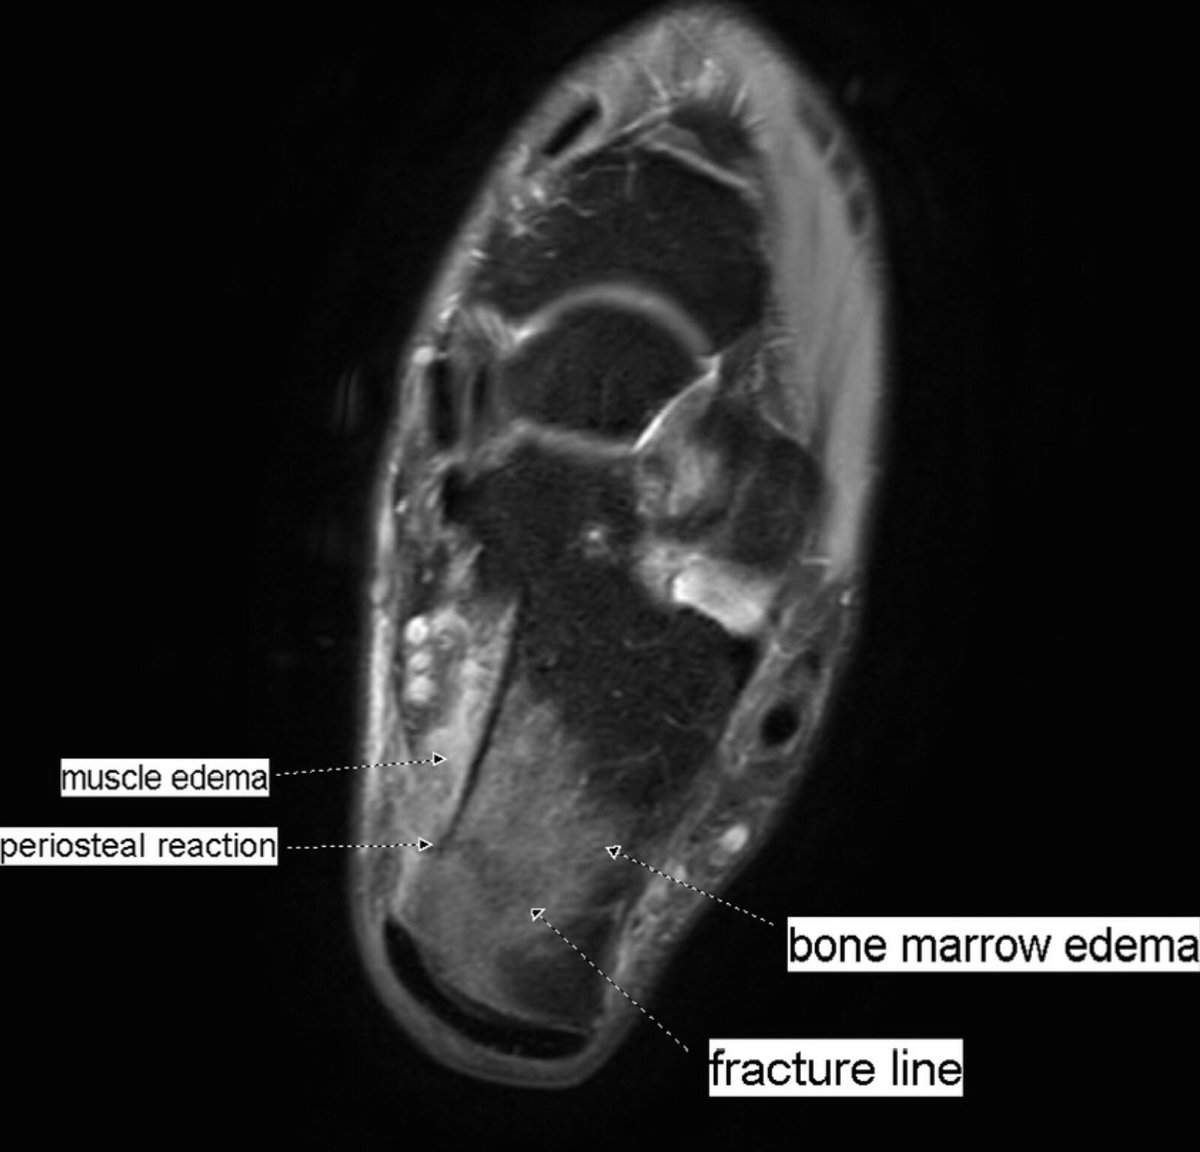

Pain worsening after rest. New MRI 18 days after to rule out again stress fracture, now clearly seen. Back to baseline examination, the oblique fracture plane was better seen as a subtle line in sagittal images.

#peerlearning#MSKrad#foot#orthopaedicspic.twitter.com/HtDYoFvH8V